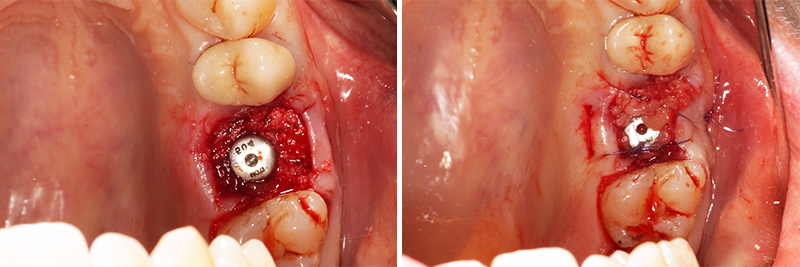

Fig. 03 : comblement du gap avec sticky bone* et xénogreffe porcine. Mise en place d’une vis de cicatrisation, membrane de PRF en couverture, sutures 5-0 résorbables afin de maintenir le PRF en place.

Fig. 03 : comblement du gap avec sticky bone* et xénogreffe porcine. Mise en place d’une vis de cicatrisation, membrane de PRF en couverture, sutures 5-0 résorbables afin de maintenir le PRF en place.

*Le sticky bone est un dérivé du PRF qui permet d’obtenir par ajout à notre biomatériau de PRF liquide, un biomatériau visqueux. Cela facilite grandement sa manipulation au-delà du fait que l’on apporte directement au contact du biomatériau des facteurs de croissance issu du PRF.

Fig. 05 : sticky bone.